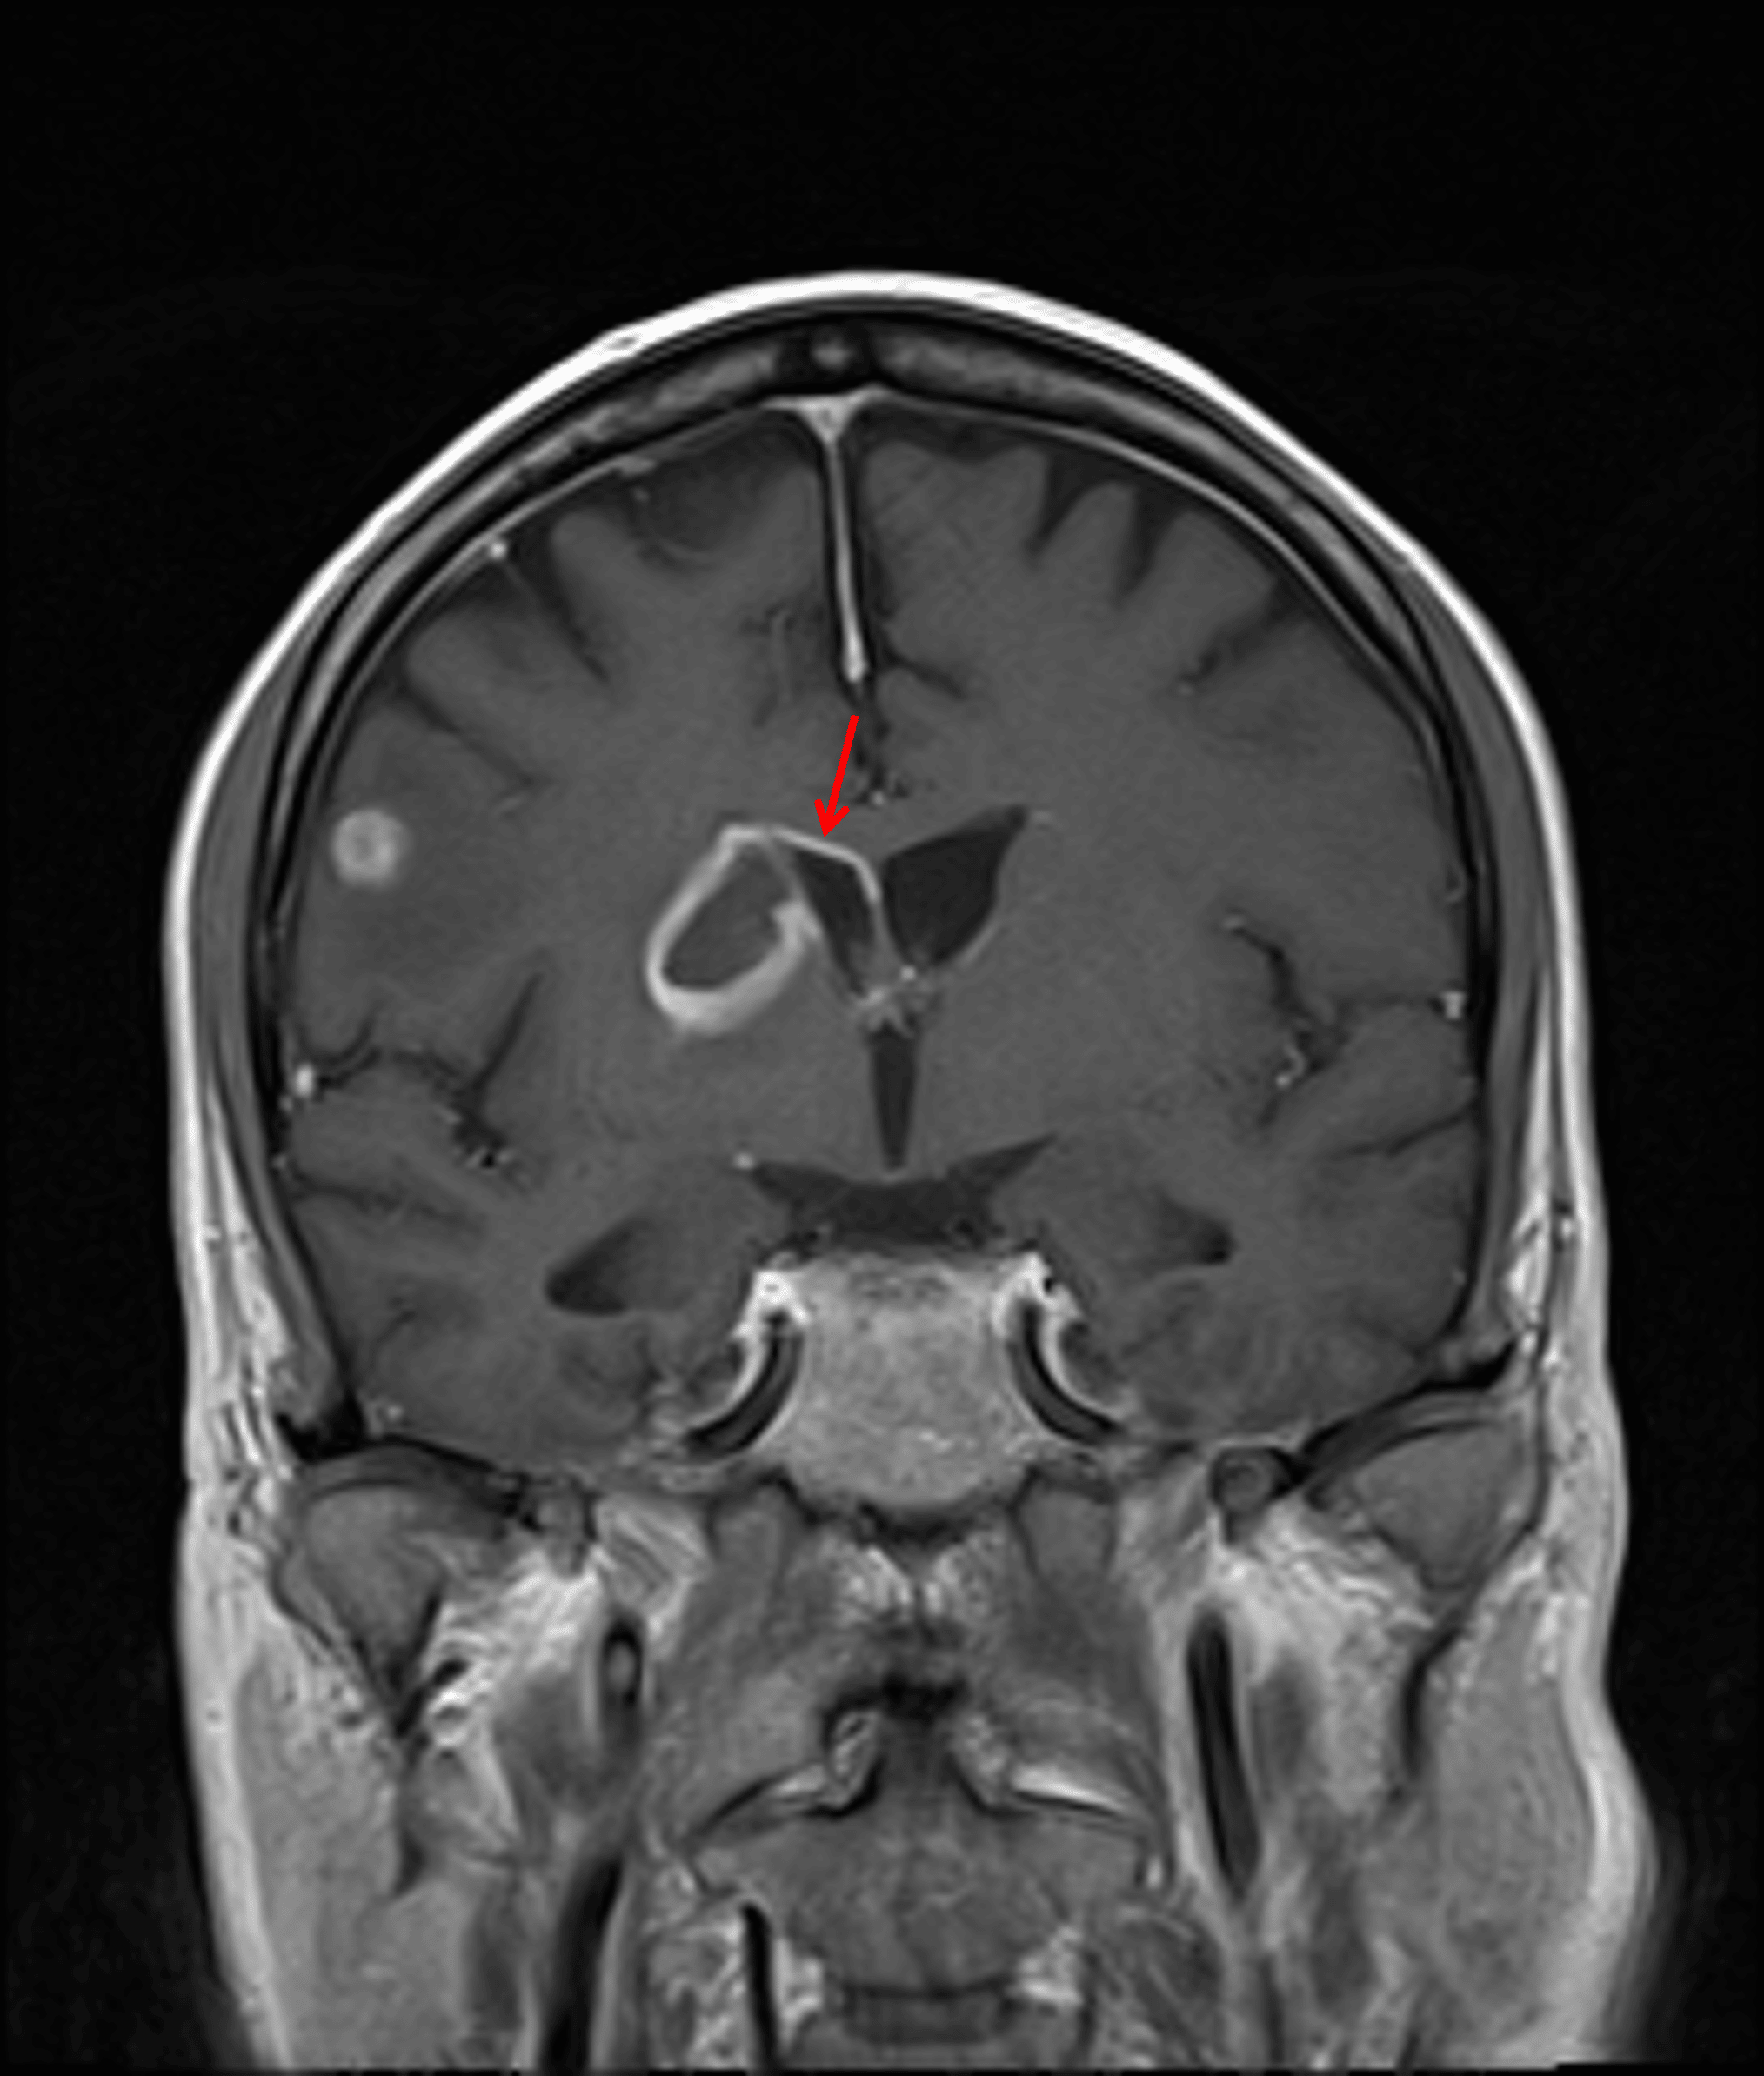

Peripherally-enhancing lesion with central restricted diffusion in the right basal ganglia and internal capsule (red arrows), highly concerning for a pyogenic abscess. Close proximity to the ventricular margin increases the risk for ventriculitis.

Enhancement extending along the superior margin of the right lateral ventricle (red arrow), which raises concern for developing ventriculitis.